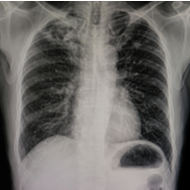

Wat is longfibrose?

Longfibrose is een chronische aandoening waarbij er bindweefsel, of littekenweefsel, gevormd wordt in de longen. Het gevolg is dat de wand van de longen dikker wordt en het lichaam onvoldoende zuurstof kan opnemen.